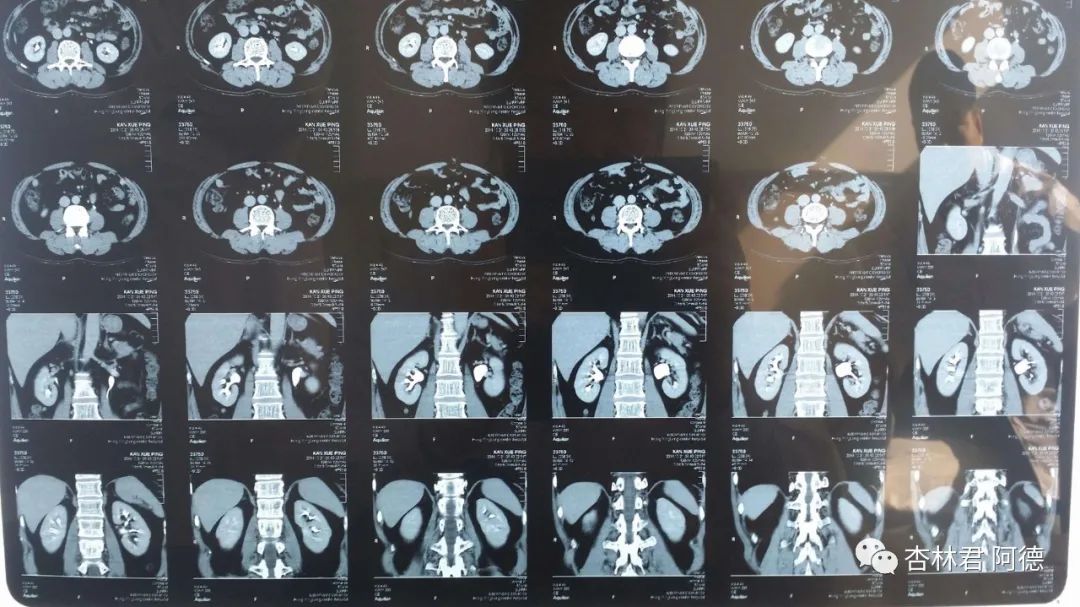

2. 客观检查资料。包括各种检查结构,比如胸片、CT、心电图、胃镜、抽血化验等等,拍这些时要注意,文字报告也不算一手资料,胸片或CT,要有黑色的那些胶片图片,当然,如果有电子版的最好,比如现在很多医院可以直接在公众号上查询并下载检查结果,包括原始图片,医生判断你的病情,一般都要看图片的,化验结构则要看具体数值。所以你用手机拍下来或者下载保存在特定的文件夹里,只要手机不丢失,你的病历资料就一直随身带,不管去哪里看病,手机打开一看,就知道,免得重复检查。胸片、CT或磁共振的胶片可以用电脑显示器做阅片等,就是打开word文档新建空白页,放满全屏,再把胶片紧贴上去,再用手机拍照,就可以获得清晰的图片。